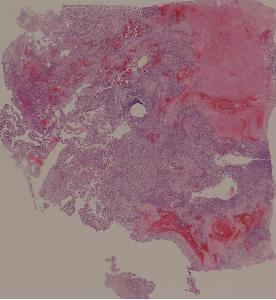

34.骨肉瘤

低倍视野